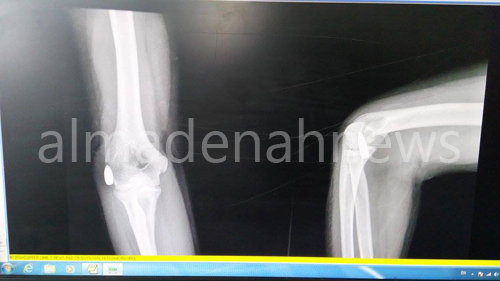

صورة اشعة تظهر موقع الرصاصة :